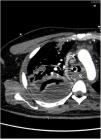

A 38-year-old man with no relevant medical history was hospitalized in the intensive care unit with fever and nonspecific respiratory symptoms, which rapidly progressed to severe respiratory failure, septic shock, and multiple organ failure. He required vasopressor support, invasive ventilation, and antibiotic treatment with penicillin, clindamycin, and linezolid after Streptococcus pyogenes was isolated in respiratory samples and blood cultures. Despite treatment, fever persisted, as did a consolidation on the chest X-ray (Figure 1). Computed tomography (Figure 2) revealed necrosis and a lung abscess in the right upper lobe. This case highlights a severe presentation of invasive Streptococcus pyogenes infection, emphasizing the need to consider this etiology in the differential diagnosis, even in patients without known risk factors.